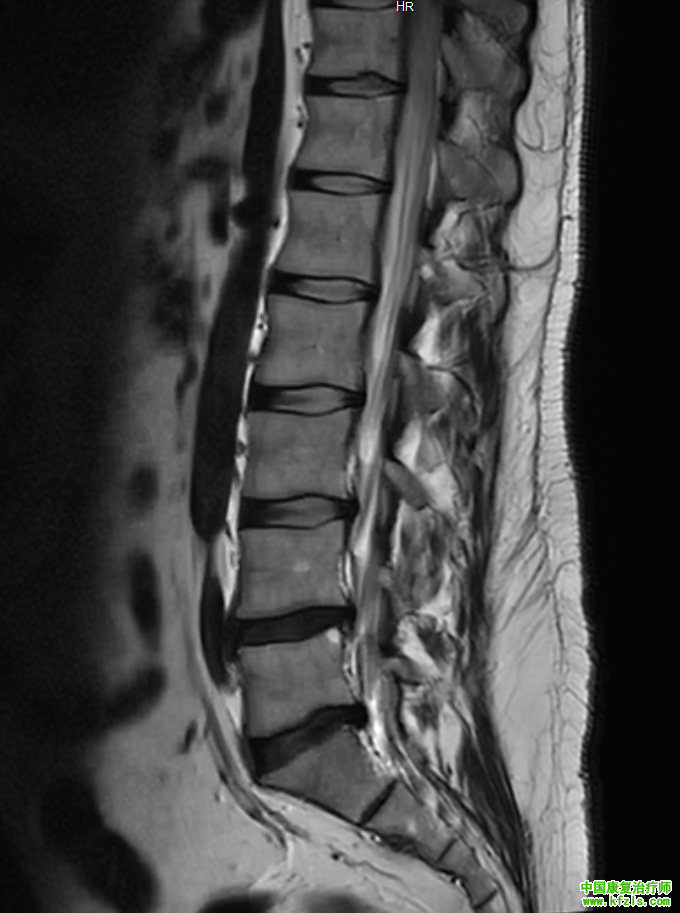

一位34岁绘画老师,男性,主诉是腰部疼痛,伴随右侧放射性麻木到大腿,长时间坐着酸胀感增加,无法搬重物,弯腰疼痛。医院拍片发现双侧椎间孔狭窄,L4/L5,L5/S1椎间盘突出,卡压神经根。直腿抬高试验阳性,slump试验阳性,弯腰测试阳性。

f4940fd6cb609653082a80c604d593b3.png

a00343da74c7834a7b73f62d4cb96ae3.png

3fbf834e35c48b70b4481a499a228fa5.png

*根据以上症状,我们给出了具体康复治疗方案